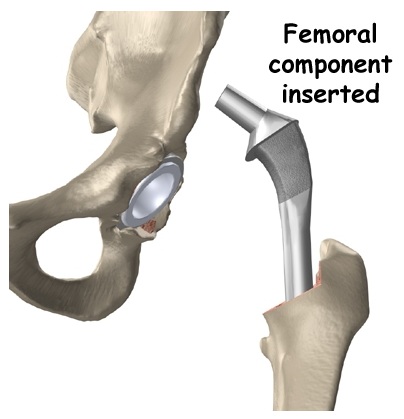

Bước 4: Sửa soạn ống tuỷ xương đùi. Việc sửa soạn ống tuỷ xương đùi rất quan trọng, đảm bảo việc liên kết giữa phần chuôi của bộ khớp háng nhân tạo và xương đùi có thể được liên kết tốt.

Bước 5: Đặt chuôi khớp nhân tạo. Chuôi khớp sẽ được đặt vào trong ống tuỷ và được cố định. Nếu là bộ khớp nhân tạo có xi măng, chuôi khớp sẽ được cố định bằng xi măng sinh học. Nếu là bộ khớp nhân tạo không có xi măng, chuôi khớp sẽ được cố định nhờ 2 yếu tố: 1) Sự nén chặt( Press fit); 2) Sự phát triển của xương mới bám chặt vào chuôi khớp nhân tạo nhờ cấu trúc của bề mặt chuôi và chuôi được phủ 1 lớp đặc biệt kích thích xương phát triển vào.

Bước 6: Lắp chỏm khớp nhân tạo, kiểm tra chiều dài chi và sự vững của khớp. Chỏm khớp nhân tạo có nhiều sự lựa chọn, giúp cho bác sỹ có thể điều chỉnh để có thể đạt được chiều dài chi lý tưởng và khớp vững.

Bước 7: Hoàn tất. Đặt khớp háng nhân tạo, kiểm tra lần cuối cùng sự vững của khớp.